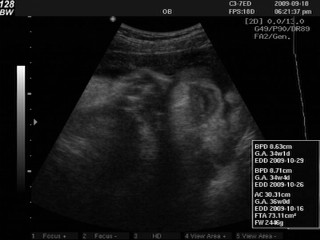

何必呢這次很傷腦筋!(左邊是何必呢的大嘴巴照 XD)

因為這個念頭,所以有點像是臨時起意的去了一趟《滿意》找吳柏瑜醫師,結果不找還好,一找簡直就是讓我煩惱到不得了,這十幾天,何必呢竟然沒有長大!!